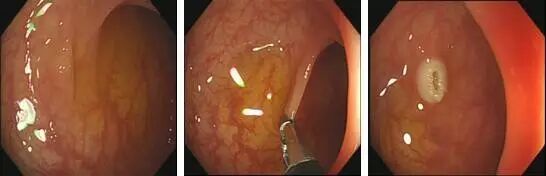

一般较小的(直径<5mm),在行胃肠镜检查时,医生会直接用活检钳钳取。见下图:

为什么说热活检钳胃肠息肉是怎么长出来的?有什么危害?如何预防和治疗?_https://www.jmylbn.com_新闻资讯_第7张1.发现息肉;2.活检钳夹住息肉;3.钳除息肉